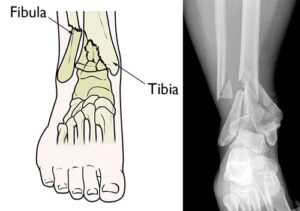

(Left) A pilon fracture often affects both bones of the lower leg. (Right) In this x-ray, both the tibia and fibula are fractured and the pieces of bone are severely displaced.